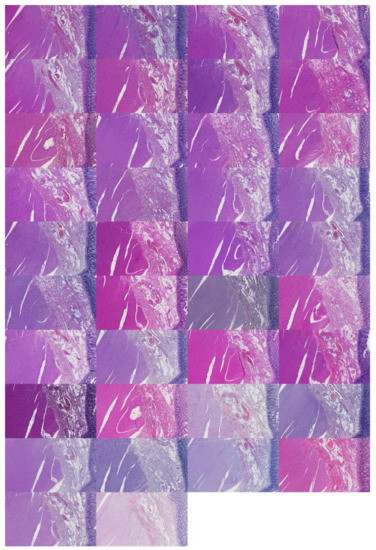

Figure A7.

Skin examples visualized by descending silhouette score within the first found cluster (C1). Silhouette values descend in the left direction from the left-most example in the first row.

Figure A8.

Skin examples visualized by descending silhouette score within the second cluster found (C2). Silhouette values descend in the left direction from the left-most example in the first row.